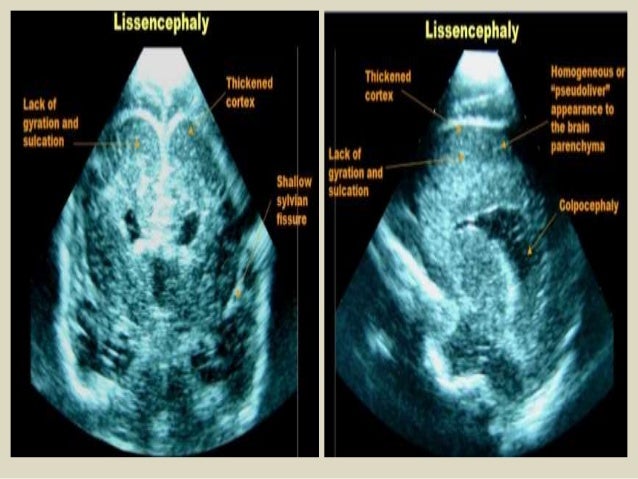

45. 45. Coronal and parasagittal USG demonstrating colpocephaly in a patient with agenesis of corpus callosum. Also, there is hypoplasia of the cerebellum, mainly involving the right lobe